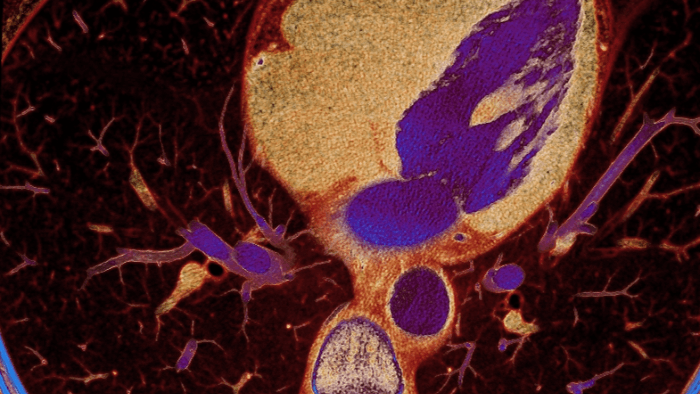

Unlike traditional CT images, spectral-detector CT images capture spectral information 100% of the time —without special planning or set-up. That means you can analyze the spectral data in any image retrospectively, using a variety of spectral viewing tools. You can, for example, adjust the monoenergetic level or get Zeffective maps.

Can you see the difference?

Move the slider to reveal spectral results when compared to conventional CT.

Conventional CT Spectral result